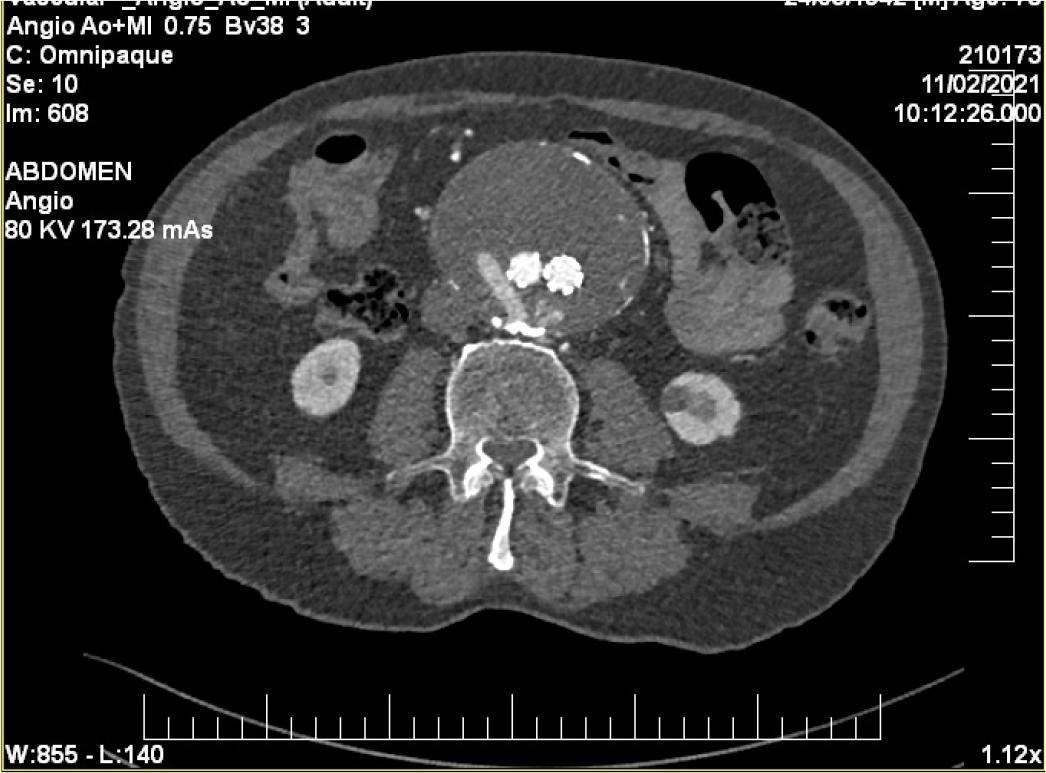

For a complete evaluation of the aneurysm, we performed a CTA of the aorta a few days after the procedure, that showed a type II endoleak, without evidence of aneurysm enlargement (Figure 4).

Computed Tomography Angiography - 3D reconstruction of the aorta (a) before, and (b) after aortic endo-graft implant.

Given the patient’s high surgical risk, the Heart Team decided that TAVR was the most appropriate management strategy. As part of the pre-procedural workup, a computed tomography angiography (CTA) was performed, which revealed a 55/60 mm infrarenal AAA characterized by a long infrarenal neck with mural thrombus and limited calcification. Additionally, the CTA identified a 4 cm aneurysm involving the right common iliac artery (RCIA), with parietal thrombosis, significant calcifications, and a residual lumen measuring 18 mm (Figure 6).

Computed Tomography Angiography showing the AAA and the RCIA aneurysm. An accessory right renal artery is also described.